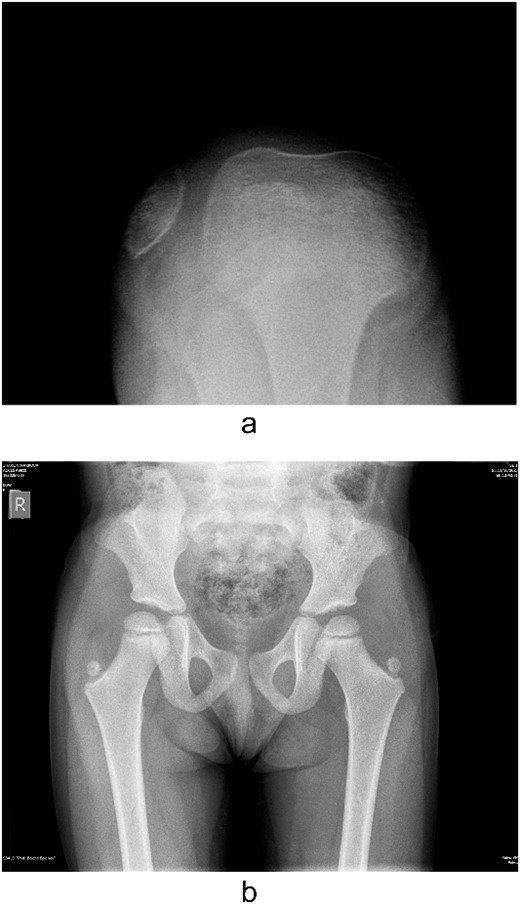

Several radiographs were taken, showing the pathognomonic bilateral iliac horns [3], normal-shaped, without signs of hypoplasia, radio-humeral joint. Both patellae were hypoplastic, with complete lateral dislocation of the right patella, as distinguished in the skyline Merchant view (Fig. 4).